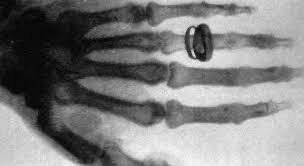

Primera Imagen de Rayos X

Se muestra la mano de Bertha Roentgen. Se pudo demostrar que esta fluorescencia ocurríais a pesar de colocar diferentes objetos entre el tubo y la superficie fluorescente, mientras que el plomo no permitía el paso de estos nuevos "rayos"